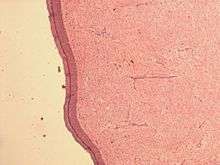

| Micrograph of an atrial myxoma. H&E stain. | |